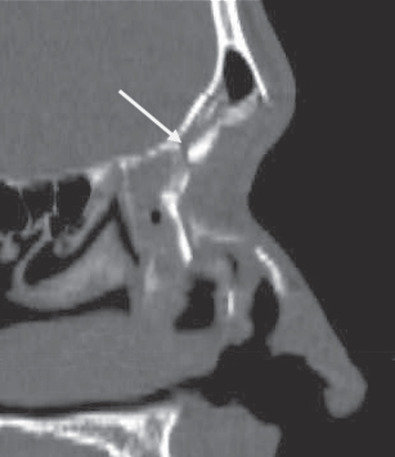

The gold standard radiographic examination for traumatic injuries of the facial skeleton is a thin cut (≤1 mm) computed tomography (CT) scan. To help improve diagnostic accuracy, these images should be reformatted into coronal, sagittal, and 3-dimensional reconstructions. The axial images are preferred for evaluation of the anterior and posterior table ( Fig. 1.7.4 ); sagittal images for the frontal sinus outflow tract and skull base ( Fig. 1.7.5 ); and the coronal images for the orbital roof/sinus floor ( Fig. 1.7.6 ). Three-dimensional reconstructions ( Fig. 1.7.7 ) offer a comprehensive view of the injury. They are helpful to assist in surgical planning, facilitate patient education, and delineate the size/location of bone fragments, which can reduce the need for soft tissue dissection.